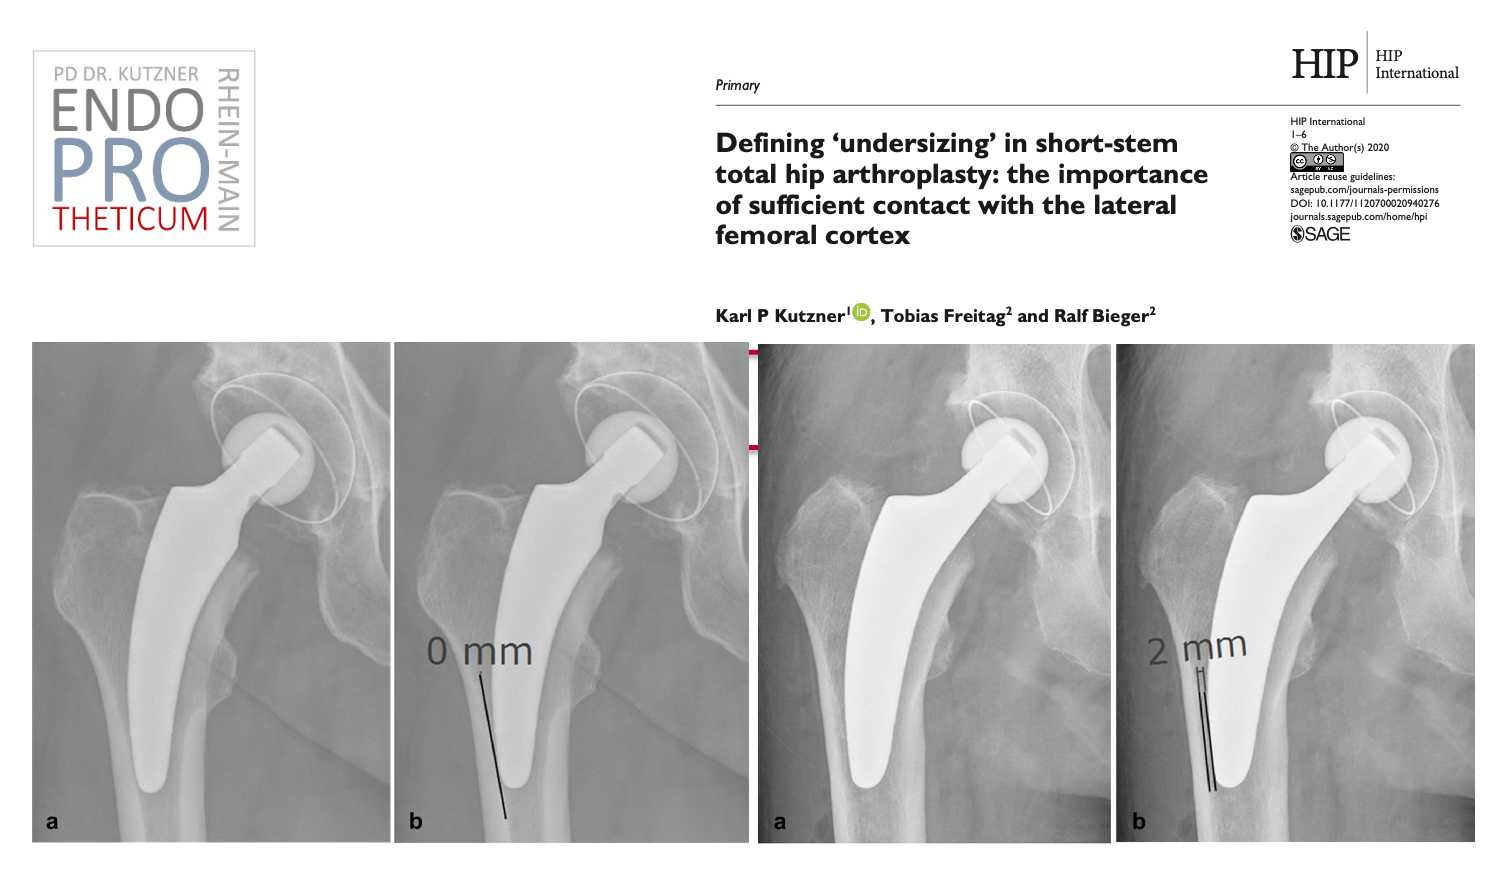

El concepto de vástagos cortos modernos guiados por calcar en la artroplastia de cadera tiene como objetivo la reconstrucción precisa de la geometría anatómica individual de la cadera. Se utiliza una técnica de implantación respetuosa con los huesos y los tejidos blandos junto con una carga fisiológica en la parte del fémur cercana a la articulación para preservar el hueso a largo plazo.